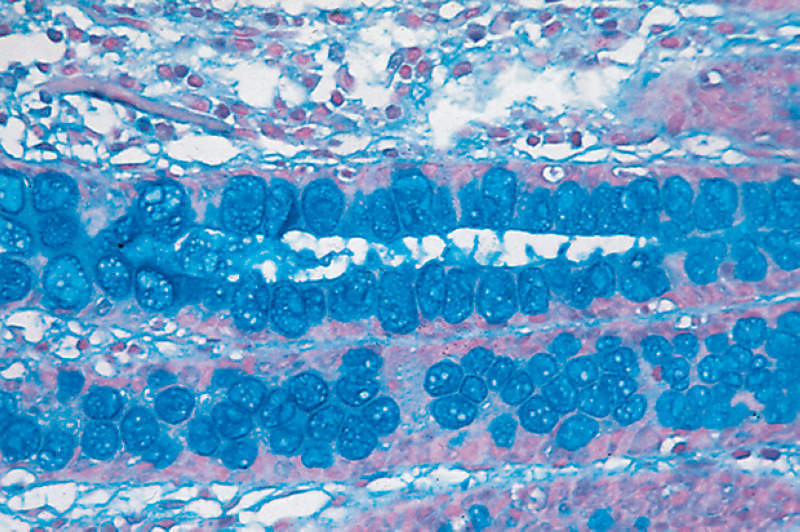

La tinción Azul Alcian es una técnica de laboratorio utilizada para colorear ciertos componentes de los tejidos, permitiendo su visualización bajo el microscopio. Es especialmente útil para detectar mucopolisacáridos ácidos, como el ácido hialurónico y los glucosaminoglicanos, que se encuentran en la matriz extracelular y en las secreciones mucosas. Esta tinción es una herramienta esencial en el diagnóstico de diversas enfermedades y en la investigación de las características estructurales de los tejidos.

El Azul Alcian tiñe específicamente los mucopolisacáridos ácidos, que son carbohidratos complejos presentes en diversas partes del cuerpo, como el tejido conectivo y las secreciones mucosas. Estos componentes juegan un papel crucial en la estructura y función de los tejidos, y su detección es vital para diagnosticar y estudiar enfermedades relacionadas con la acumulación anormal de estas sustancias.

- Cartílago: El Azul Alcian es útil para teñir cartílago, ya que este tejido contiene altas concentraciones de glucosaminoglicanos.